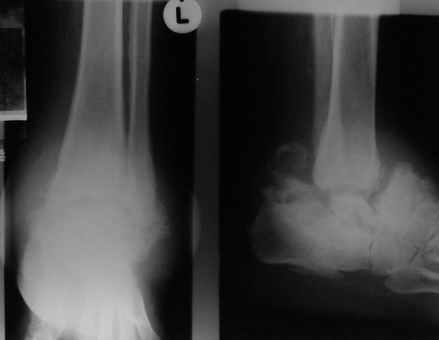

Кто шустрый - при какой патологии встречается так называемые "суставы Шарко"?Второе приобретение доктора Эмануэла мне понравилось своим романтическим названием: Candle bone - <кость-в-виде-оплывающей-свечи> : Просто редкая патология:

VR>Второе приобретение доктора Эмануэла мне понравилось своим романтическим названием: Candle bone - <кость-в-виде-оплывающей-свечи> : Просто редкая патология:

Остеосклероз при этом заболевании захватывает не всю кость по окружности, а простирается слегка волнистой

полосой вдоль длинной оси конечности (рис. 223, К), переходя через линию суставов на другие кости. Таким образом,

может оказаться пораженной целая верхняя или нижняя конечность или больший или меньший ее периферический участок,

например, часть лопатки, полуцилиндр плечевой кости, часть цилиндра лучевой кости и скелет II пальца вместе с

лежащими по этой оси участками запястных костей или же часть - медиальная или латеральная - бедренной,

болынеберцовой кости с продолжением и расширением процесса на предплюсневые и плюсневые кости и соответствующие

по длиннику фаланги одного или нескольких, но никогда не всех пальцев. Описавшие эту болезнь в 1922 г. Жоани

(Joanny) и Лери (Leri) сравнивают остеосклеротические полосы с картиной, напоминающей стекающий со свечи и

застывающий стеарин или воск, отсюда и название "мелореостоз" - "стекающая вдоль конечности кость".

Отдельные случаи мелореостоза отличаются друг от друга по степени и форме склеротических участков; каждый случай

представляет свои неповторяемые особенности. В более тяжелых случаях поражения нижней конечности захвачена и

соответствующая половина таза, при локализации в верхней конечности - часть лопатки. Из парных костей поражается,

как правило, только одна: это большеберцовая или малоберцовая кость, лучевая или локтевая кость, но никогда не

Измененный корковый слой, а также уплотненные эпифизы и мелкие губчатые кости приобретают плотность слоновой

кости. Корковый слой утолщается как в сторону костномозгового канала (эндостальная форма), в большей или меньшей

степени суживая его, так и наружу (периосталь-ная форма), возвышаясь над нормальным уровнем кости и увеличивая

этим ее наружный диаметр. Поверхность "наплывов" слегка волниста, с гребневидными возвышениями и углублениями, но

всегда резко конту-рируется. Склеротические полосы и ленты бывают чаще всего сплошными, но нередко они

прерывисты, расслоены. Иногда наблюдается некоторое удлинение костей и их небольшая дугообразная деформация, а